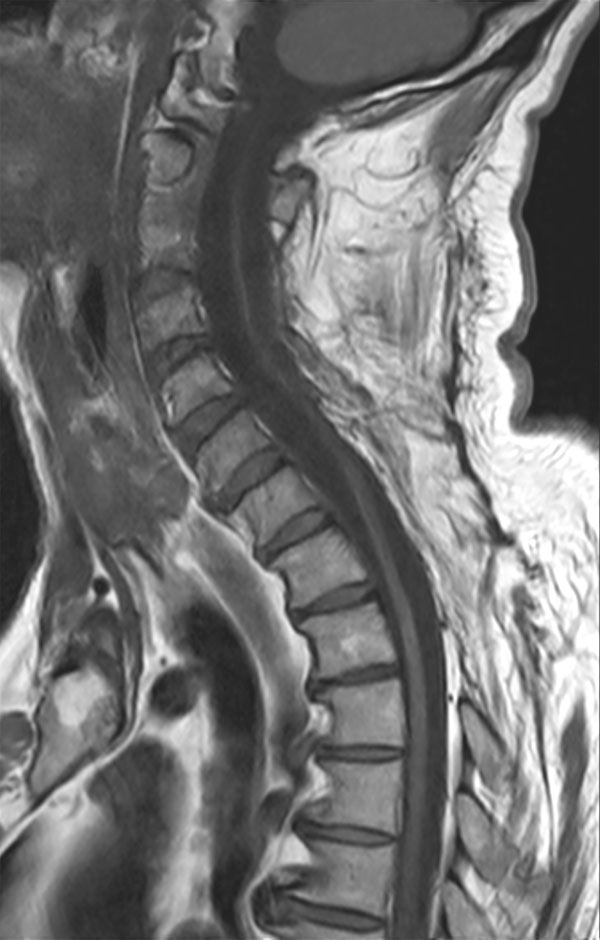

51 year-old man with poor general health and neurological disturbances. Histological examination of the surgical specimen led to the diagnosis of lipomatous ependynoma. Post surgery MRI (resected ependynoma) performed with dS HeadNeck coil with coverage till T4.